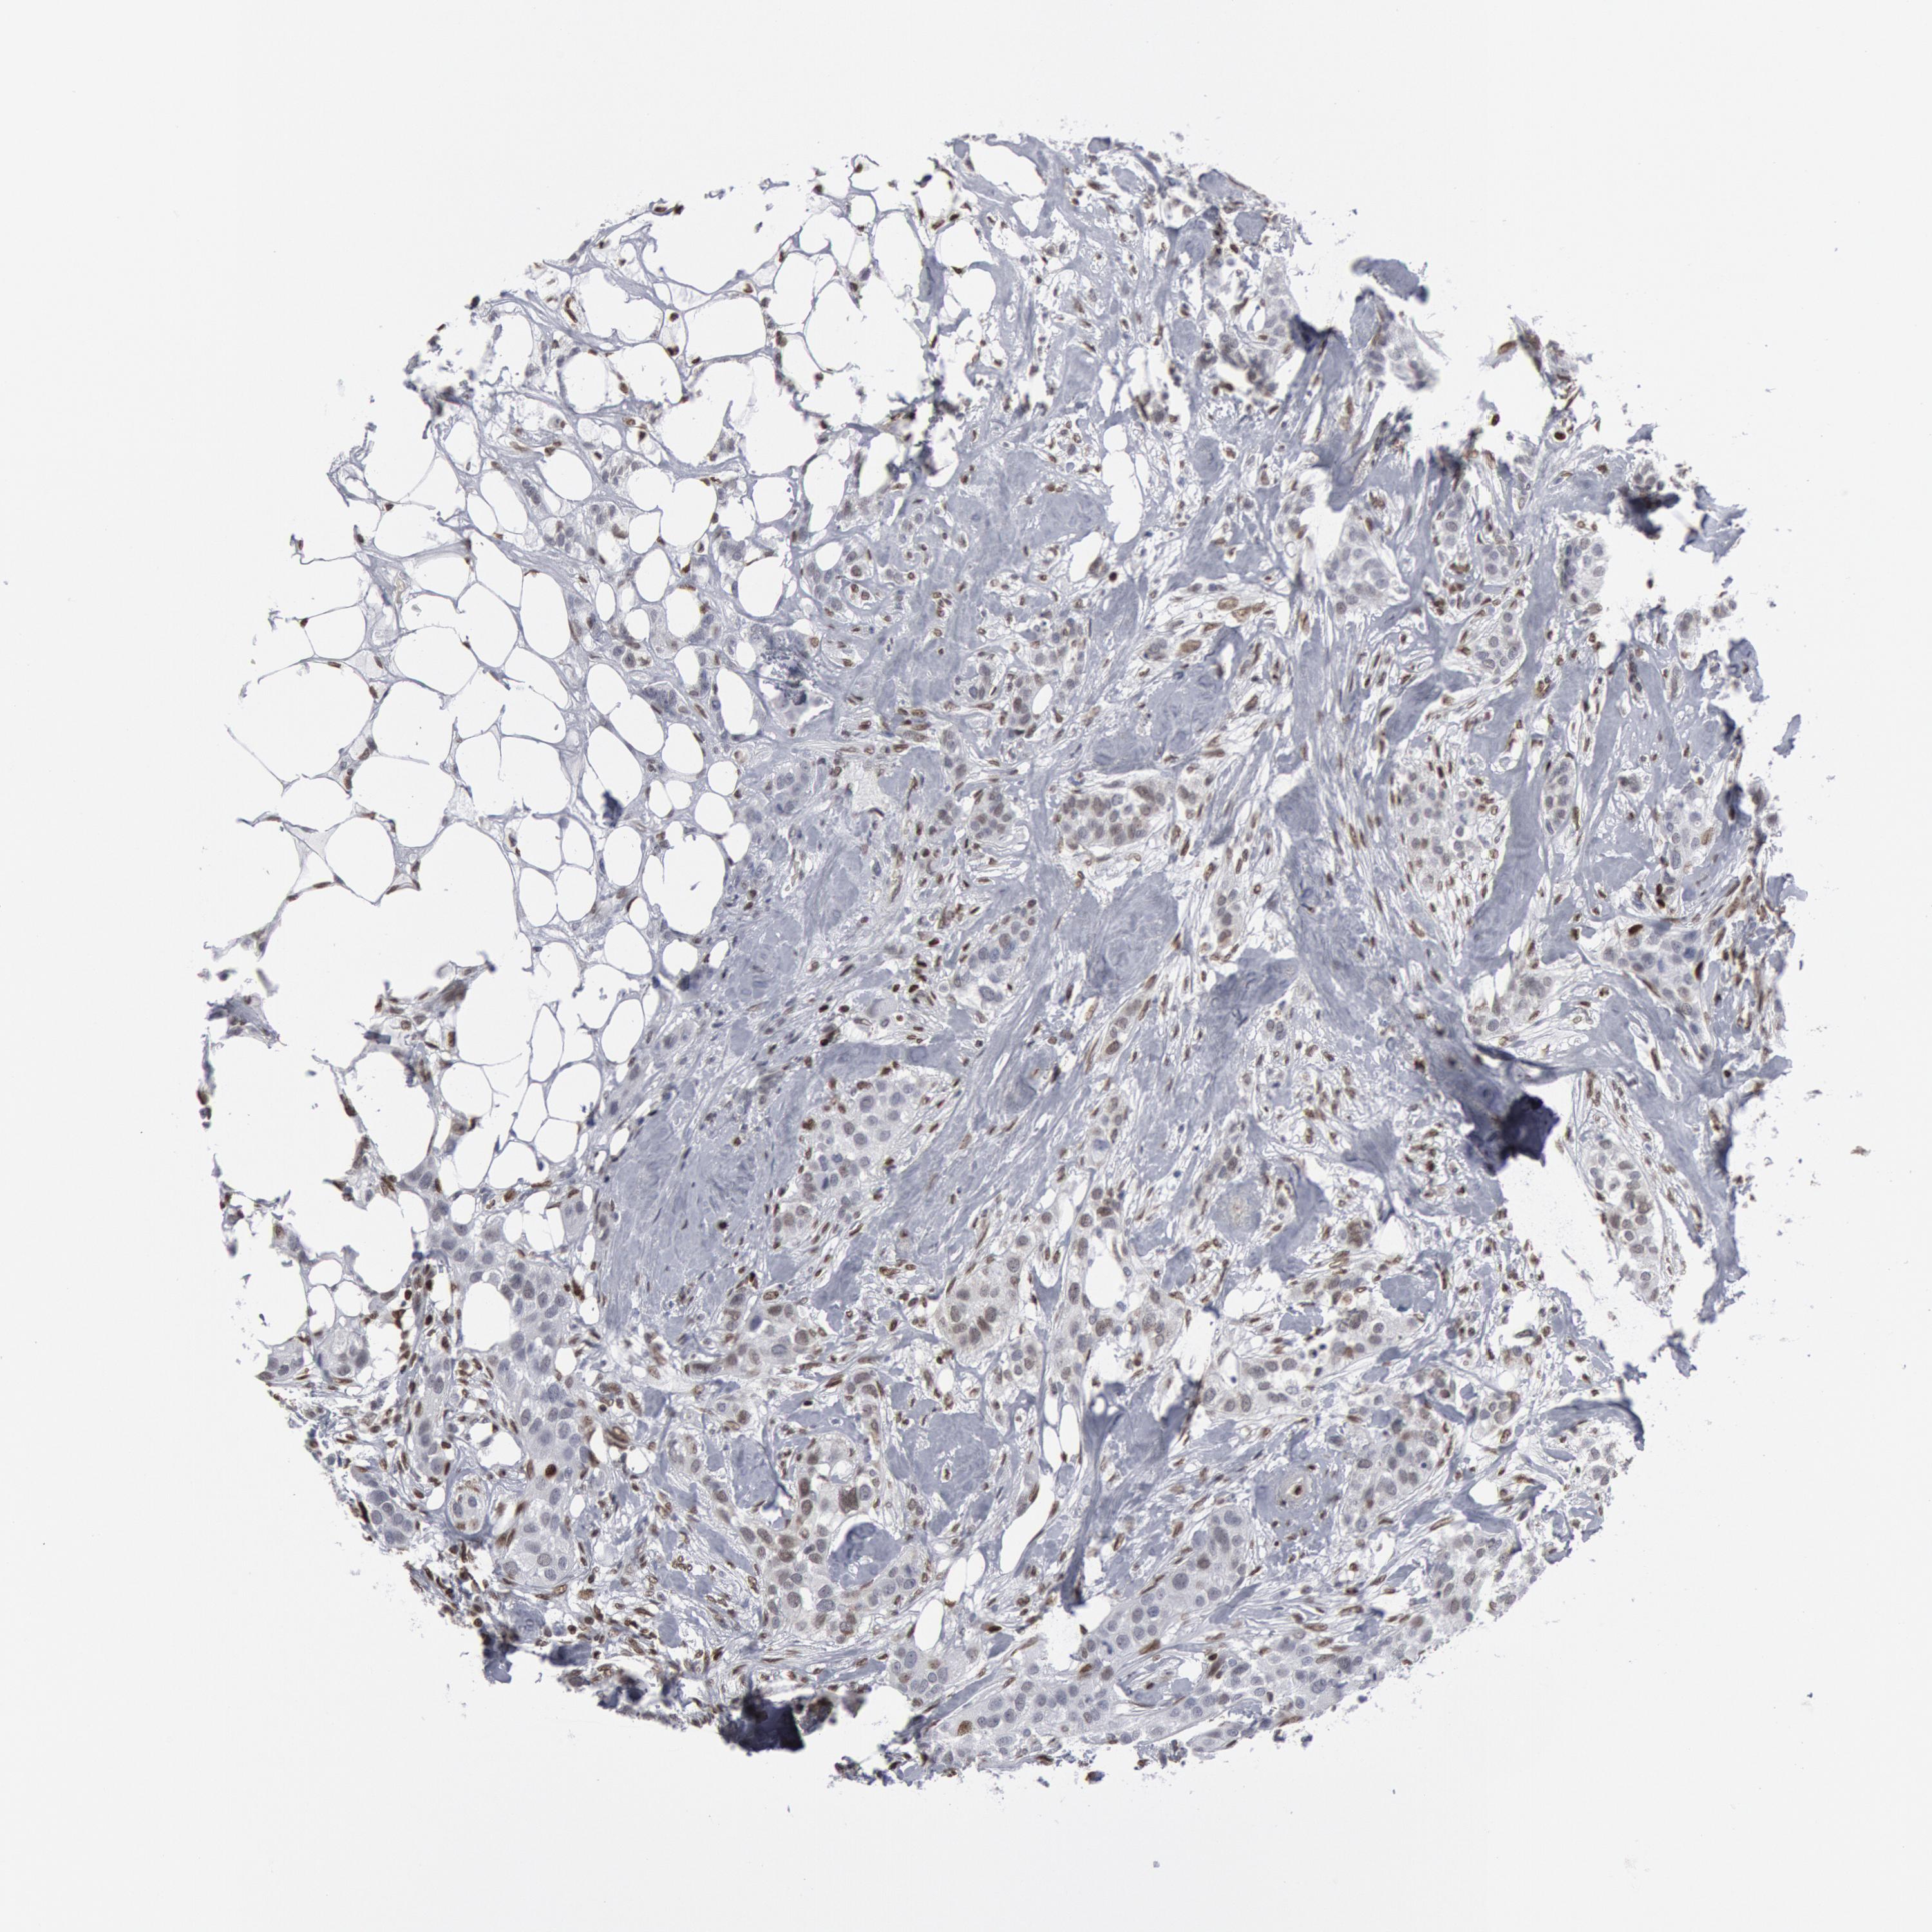

CANCER BREAST CANCER Show tissue menu

BRCA TCGA BRCA VALIDATION PROTEIN EXPRESSION